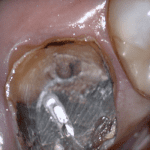

This case was scanned by two different scanners. Once by the Medit i500 and another time with the Aoralscan. Both the meshes are included so you can compare the two. It was scanned to deliver a case that retrofits a partial denture